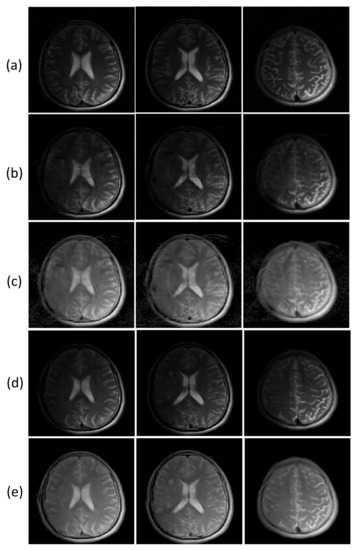

4.1. Variants of the Refinement Network

Figure 4 presents the reconstructed images from three different refinement networks: the single convolution layer, multiple convolutional layers, and dual frame U-net. Figure 5 presents the quantitative analysis of the three refinement networks. As shown in Figure 4, the images refined by the single convolution layer contain a substantial amount of structural artifacts. In addition, the image details are also deteriorated. In contrast, the images refined by the WTA and DFU have considerably improved image quality, and the image details are clear. However, the images refined by the DFU have better image details. The quantitative measures also demonstrate that the DFU can be efficiently used for the refinement of the latent features in the proposed method. The single convolutional layer shows considerably higher nMSE and lower SSIM values than the other two methods, and the DFU shows improved performance in terms of nMSE and SSIM.

Figure 4.

Comparison of three different refinement networks (Section 4.1). Two example slices of experiment results are shown. (a): Ground truth magnitude images (label images). (b–d): Reconstructed images using (b) single convolutional layer, (c) WTA, and (d) DFU.